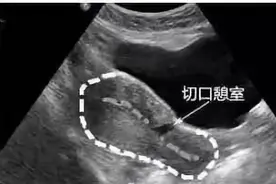

近日,济南市莱芜人民医院妇产科团队成功实施一例宫腔镜下瘢痕憩室修补术,解决了患者数年来月经经期延长的痛苦。据悉,患者自剖宫产后出现月经经期延长,由原来7天延长至15-17天不等,给生活带来诸多不便。多次检查均提示子宫瘢痕憩室,经药物治疗疗效不佳。

很多人在买房后都会试图扩大它的使用面积,比如浇筑水泥搭建一个新的阳台,分隔两层建造一个阁楼,让整个房子物尽其用。可是如果是胎儿居住的子宫被扩建,多出一个被称作“憩室”的小房间,医生提醒说:“它带来的隐患是无穷无尽的。”尤其要提醒,“单独二胎”政策放开后,有许多妈妈们跃跃欲试。

来源:【湖南日报】文字/视频 湖南日报全媒体记者 周阳乐 通讯员 吴可欣 余杨长沙市民小雪(化名)剖宫产后出现这样的烦恼:以前3-5天就干净的月经,现在变成了10多天,甚至更长,给日常生活带来了严重的不便。